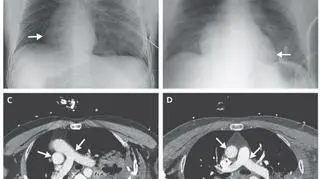

Tomografia komputerowa i rentgen motocyklisty

Źródło: The New England Journal of Medicine

Okazało się, że jest to coś dużo rzadszego. Zdjęcia rentgenowskie oraz tomografia komputerowa wykazały, że organ obrócił się o dziewięćdziesiąt stopni w prawo. Pacjent odniósł także obrażenia żeber i miał odmę płucną.

Kolejne, jeszcze bardziej szczegółowe badania wykazały, że w prawo obrócił się także pień płucny, aorta, oba przedsionki i obie komory, de facto więc całe serce.